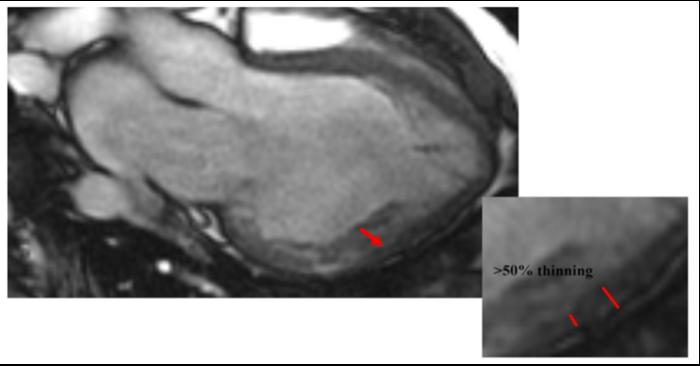

image: Abrupt thinning of heart muscle walls by over 50%, as detected by cardiac magnetic resonance imaging.

Cardiac magnetic resonance imaging has emerged as an important tool to identify patients with LVNC because of its excellent resolution. It is more accurate, reliable, and informative than traditional methods of assessing the heart, such as echocardiography. However, the current criteria for identifying LVNC patients using cardiac magnetic resonance imaging are based on information from a study with a small sample size, and they lack sensitivity. There is a risk that individuals with LVNC are being missed. More recent studies have suggested that heart muscle (myocardial) wall thinning, detectable using cardiac magnetic resonance imaging, is related to adverse clinical events and could be a valuable indicator of the disorder.

This important study has therefore validated the use of myocardial thinning, visualized via cardiac magnetic resonance imaging, as a predictor for LVNC disease severity. Incorporating myocardial thinning into medical risk assessments in the future will improve the prediction and management of adverse outcomes of LVNC patients.